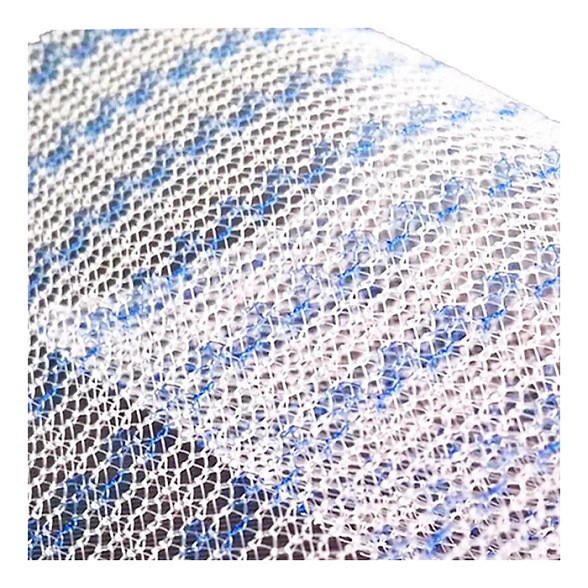

Эндопротез-сетка (сетка хирургическая) полипропиленовый для восстановительной хирургии ЭСФИЛ тяжелый, 8х12 см, Линтекс

Эндопротез-сетка полипропиленовая ЭСФИЛ тяжелый для восстановительной хирургии

Представляем вашему вниманию высококачественный хирургический имплантат — эндопротез-сетку полипропиленовую ЭСФИЛ тяжелый от известного производителя «Линтекс». Это современное решение для пластики и укрепления тканей в абдоминальной и тазовой хирургии, разработанное для обеспечения надежного и долговечного результата.

Сетка ЭСФИЛ тяжелый размером 8х12 см — это монофиламентный полипропиленовый сетчатый эндопротез с увеличенной плотностью и массой. Его ключевая особенность — высокая механическая прочность при минимальной ригидности, что позволяет эффективно закрывать обширные дефекты тканей, обеспечивая физиологичное и анатомичное восстановление.

- Отличная интеграция с тканями: Макропористая структура монофиламентной сетки способствует свободному прорастанию соединительной ткани, обеспечивая прочное сращение и снижая риск осложнений.

Благодаря макропористой структуре (размер пор более 75 мкм) сетка свободно инфильтрируется макрофагами, фибробластами и коллагеновыми волокнами. Это приводит к образованию прочного соединительнотканного рубца, который и составляет основу несущего каркаса.